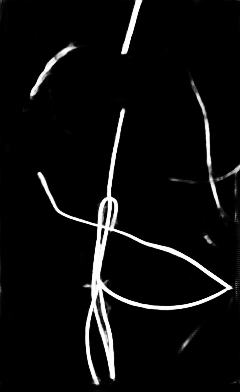

Qualitative visual examples of the raw catheter likelihood maps obtained directly from the network without any postprocessing are shown in Figure 5. It can be seen that the proposed network at the highest scale (scale 3) achieves the best visual appearance as compared to the other methods. The maps from the proposed network at scale 2 and scale 3 look much cleaner than w/oR and fcn8s. We would attribute this to the iterative refinement of the detection results by using the recurrent module. When comparing results from the proposed network at different scales, we can see that the likelihood map from the smallest scale contains almost all line-like structures, including not only catheters but also ribs and ECG leads. This is because catheters, ribs, ECG leads look similar at a smaller scale. These irrelevant line-like structures are gradually filtered out in higher scales because catheters, especially UVCs and UACs, begin to appear as two parallel edges whereas ribs and ECG leads continue to appear as a single solid line.